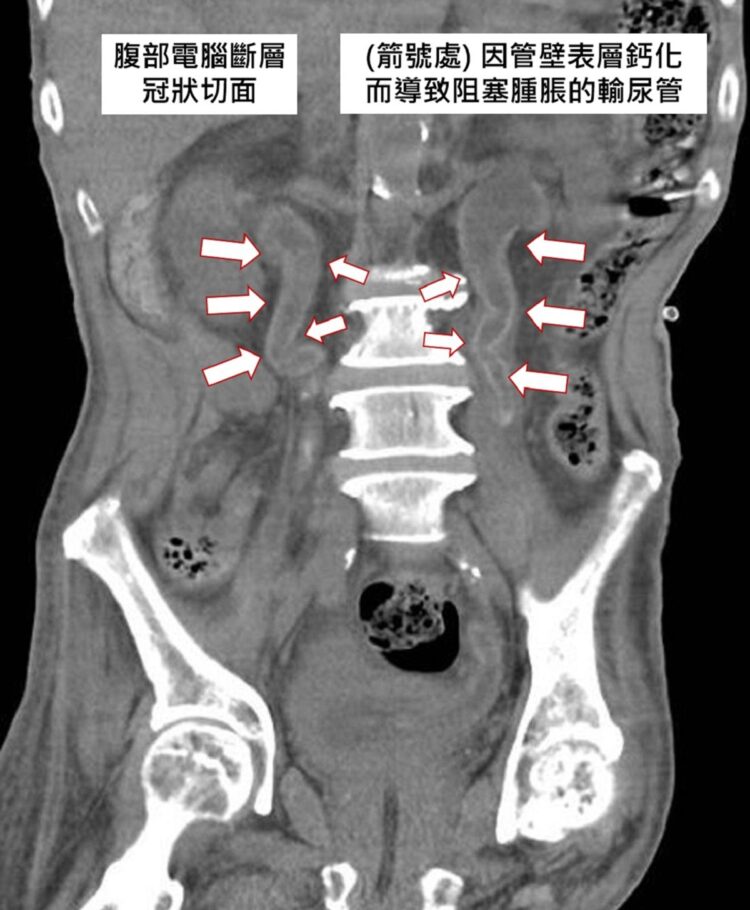

蔡旻叡指出,從超音波可發現梁男的腎臟有類似鈣化的強回音反射,但又不是典型腎臟結石,看起來滿奇怪的,腎臟科、泌尿科及感染科一起會診,進一步從腹部電腦斷層發現鈣的沈積物覆蓋在泌尿道系統的內部表面,包括腎臟髓質及輸尿管,像是一層蛋殼一樣,也可以看成內璧有如敷上一層厚厚的水泥,輸尿管因此阻塞擴大,造成水腎及慢性發炎現象。